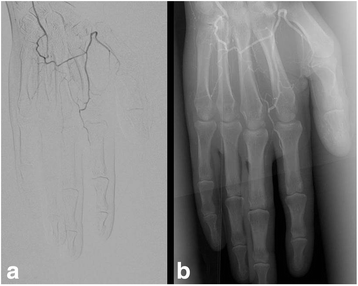

Case presentation: We report a 60-year-old Caucasian male attended our hospital with a bulky lymph node mass in the right axilla. Extirpation of a lymph node conglomerate revealed 5 melanoma lymph node metastases. Computed tomography showed a liver metastasis (diameter: 3.8 cm), several retroperitoneal metastases, bilateral metastases in the lung hilus, and prepectoral subcutaneous metastases (Stage IV; pTx, N3, M1c). Lactate dehydrogenase and S100B were slightly elevated. Combination therapy of nivolumab (1 mg/kg BW) and ipilimumab (3 mg/kg BW) was started. Three weeks after the first combination therapy he developed progressive erythema, paraesthesia and pain on the fingertips of both hands. Both cold and warmth was not well tolerated by the patient. Complete work-up excluded associated conditions or factors such as haematological disorders, rheumatologic disorders, hypertension, diabetes or smoking. Treatment was initiated with prostacyclin 20 μg twice daily and oral prednisolone 50 mg in tapering dosage. However, prostacyclin was stopped after the first applications because the pain increased during infusion. The second course of nivolumab and ipilimumab was administered. About 2 weeks later, the patient presented with increased pain and small subungual necrosis. We treated the patient with oral analgetics and intravenous prednisolone 500 mg in tapering dosage. On digital substraction angiography occlusion of all arteries of the fingers was demonstrated. Further rheologic and anti-melanoma treatments were refused by the patient. About 2 months after the second course of nivolumab and ipilimumab combination therapy several fingers showed severe gangrene which finally led to amputations of end phalanges of several fingers. Histopathology did not reveal evidence for vasculitis or other primary vascular pathologies. During the following 2 months the patient experienced dramatic progress of his metastatic disease and finally died at multi-organ failure.